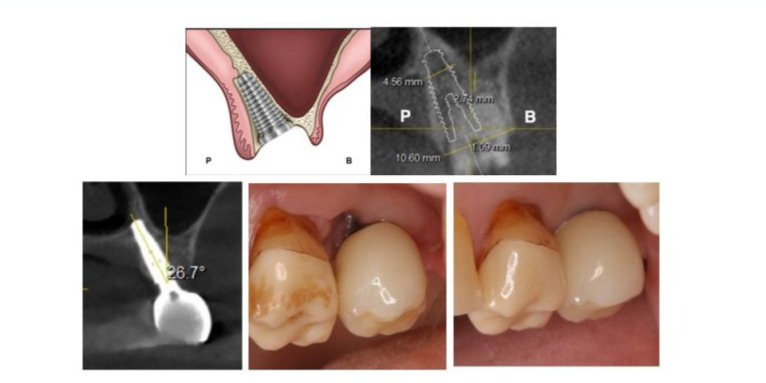

Figures 4a to 4e: a. A schema of a type E socket: L, Lingual and B, Buccal. Please pay attention to the position of the implant platform; b. A treatment plan with coronal sectional image for a case of healthy 51-year-old male patient company employee who visited for tooth pain. A type E socket without any septal and root sockets. Furthermore, there might be a lack of axial bone required for initial stability; c. Existing gap of about 5 mm; d. A periapical radiograph after 3 years; e. Soft tissue thickness of about 3 mm observed on the new bone into the gap.

Figures. 5a to 5e: a. A Schema of a type E socket: P: Palatal and B: Buccal;b. A treatment plan with coronal sectional image for a case of healthy 73-year-old female patient occupied housewife who visited for tooth pain for an implant placement in the type E socket; c. The implant with a 26.7-degree angle to the occlusal plane with sectional image 3 years after the surgery; d. Buccal view at the time of restoration with soft tissue placed 2 weeks after the surgery; e. Buccal view of the restoration with soft tissue 12 weeks after the surgery.

Treatment of a Type E Socket in the Maxilla: Case 7.

The tilted implant in a type E socket in the maxilla might have a higher ITV than an axial implant. The reason is that, whereas axial implants rely on the cortical bone plate of the maxillary sinus floor alone for stability, a tilted implant can be inserted into the region surrounded by two or three walls: the lateral cortical bone of the maxillary sinus floor, the cortical bone plate of the palate, and sometimes the cortical plate of bone on the nasal cavity floor (Figure. 5a-c). Therefore, a longer implant and higher ITV than an axial implant can be expected, if anatomical conditions permit. Under these circumstances, minimal flap or flapless elevation under good visibility would be possible. The soft tissue depression created at the time of surgery appears to gradually return to a normal shape over a period of approximately 6 to 12 months as bone forms in the gap area (Figure 5d,e).